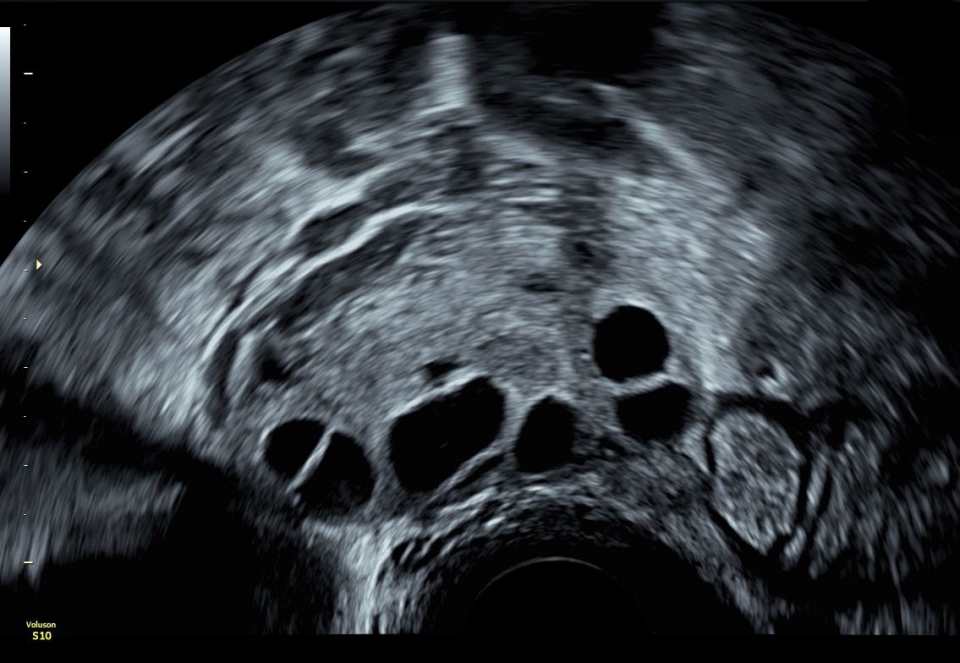

УЗИ аппарат Voluson S10 позволяет проводить обследования высочайшего уровня с максимальной точностью диагностики. Благодаря технологии Voluson Core Architecture достигнут высокий уровень качества изображений с возможностью последующей обработки и анализа даже после проведения скрининга. Технология HDlive делает изображения удивительно реалистичными и объемными.

Ультразвуковой аппарат Voluson S10 оснащен чувствительным цветовым допплером, который позволяет оценить кровоток и анатомию сосудов, обеспечивая полную информацию о состоянии плода и околоплодной жидкости. Кроме того, на Voluson S10 установлен большой 22-дюймовый экран, который при использовании трехмерного шарнира может поворачиваться в различных плоскостях, обеспечивая удобство как для пациента, так и для врача.

• SonoAVC (Автоматический расчет объема): Эта функция позволяет визуализировать и рассчитывать размеры и объем гипоэхогенных образований, таких как фолликулы яичника или структуры головного мозга плода. Она помогает в оценке этих образований и отслеживании их изменений в течение времени.